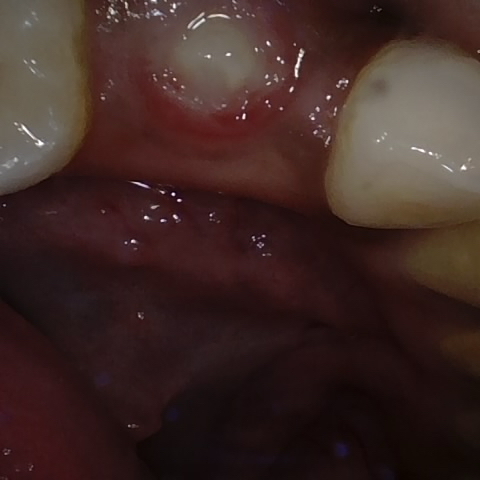

Annotated as "Good"